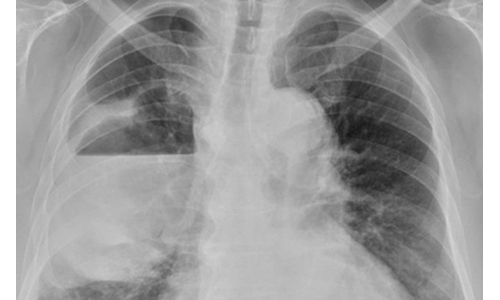

68歲的張先生為高血壓患者,平時有抽菸和喝酒習慣,突然出現咳嗽和發燒症狀,時間長達兩周,在診所拿藥服用後仍未改善。最後除了發燒和咳嗽加劇外,還合併右側胸痛及呼吸漸喘等症狀,才至醫院治療。台南市立醫院胸腔暨食道外科醫師方副吉表示,患者出現14公分大的肺膿瘍,因此緊急以廣泛性抗生素治療,狀況才開始好轉。

肺膿瘍是一種肺實質化膿性的細菌感染,會造成組織壞死,引發肺實質開洞而形成空氣液面變化。方副吉說,為治療患者的右側肺膿瘍,安排電腦斷層,經皮胸腔導管引流出約700 cc帶有惡臭味的黃白色膿液後,再治療呼吸喘的症狀,患者病情才進一步改善。至於患者的膿液,培養的結果是厭氧性細菌,必須使用抗生素治療至少四周以上。雖然感染狀況沒擴散,但仍面臨隨時要以手術介入可能。